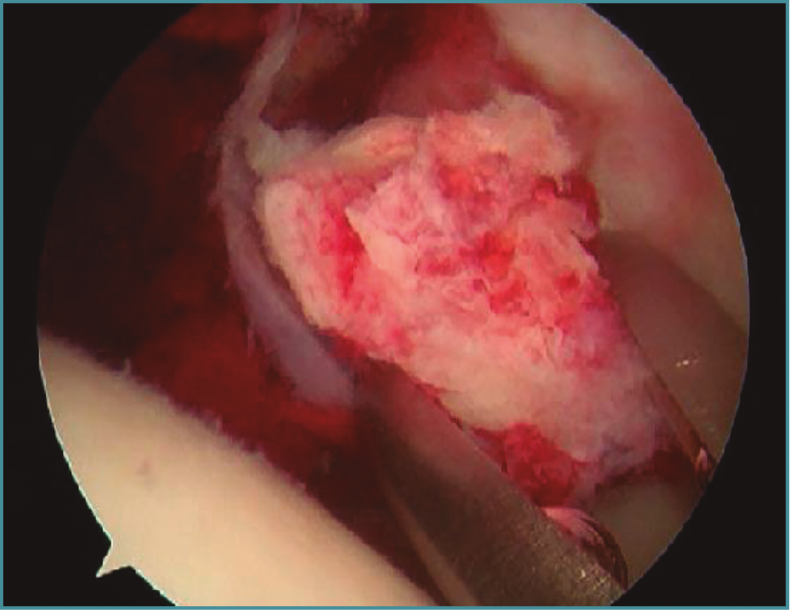

Se trata de un vVarón de 22 años que sufre luxación posterior de cadera izquierda y fractura conminuta de rótula izquierda tras sufrir un accidente de tráfico. Se trata mediante reducción cerrada de la cadera en las 6 primeras horas posteriores a la luxación y cerclaje de rótula, apreciándose una fractura de la ceja posterior no desplazada del acetábulo de la cadera luxada. La reducción fue satisfactoria, pero la TC muestra la presencia de fragmentos intraarticulares. Se le realizó tratamiento artroscópico de cadera con extracción de fragmentos (Figura 4).

Figura 4. Extracción del fragmento óseo intraarticular mediante técnica artroscópica.